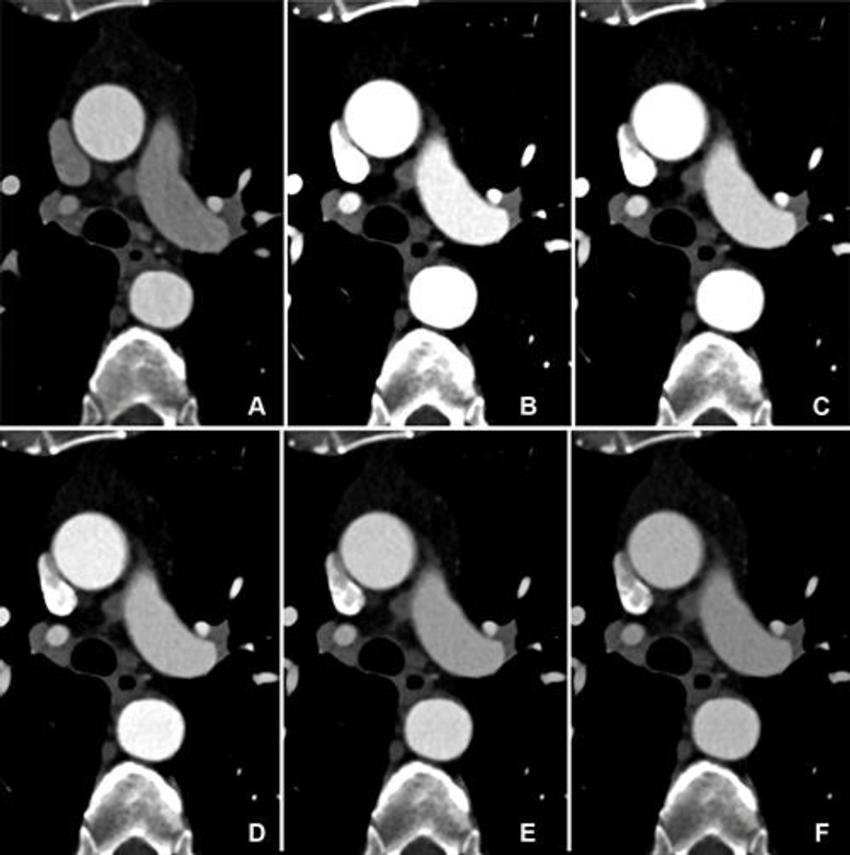

Figure 3. Comparison of image quality between EID CT and PCD CT using identical contrast media protocol and matched radiation dose. Transverse CTA images show the thoracic aorta at the level of the pulmonary trunk in a 62-year-old man in group 1, shown using identical window settings (window center: 350 HU, window width: 1000 HU). (A) Images from scans performed with a third-generation dual-source CT system with EIDs. (B–F) Images from PCD CT with VMI at energy levels from 40 to 60 keV. Time interval between scans was 11 months. Both scans were performed with the same contrast media protocol (volume, 70 mL). Note the higher vessel attenuation at lower energy levels for PCD CT. CTA = CT angiography, EID = energy-integrating detector, PCD = photon-counting detector, VMI = virtual monoenergetic images.